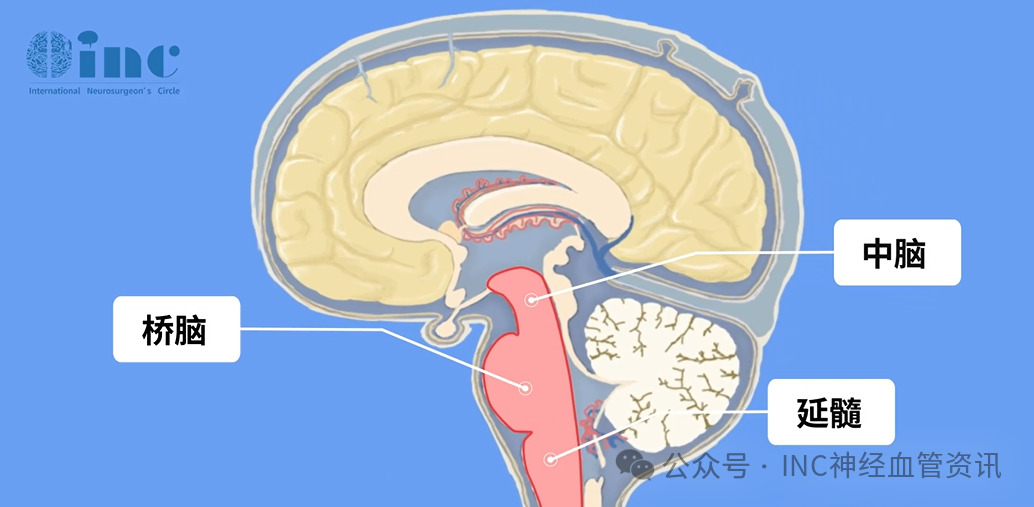

深夜熟睡中突发昏迷、日常活动时突然肢体瘫痪这些看似毫无预兆的急症,背后可能藏着一个危险的元凶:脑干海绵状血管瘤。 脑干作为掌控呼吸、心跳的生命中枢,仅拇指大小的脑干一旦出...